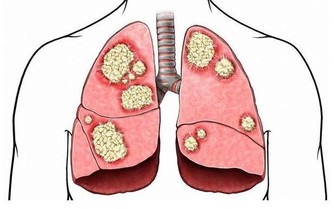

臨床上,另一名50多歲民眾,檢查出貧血症狀,且腎臟功能異常被轉診至醫院,確診為多發性骨髓癌,經過標靶藥物合併化學治療後,貧血症狀也逐漸改善;林明恩醫師說,若抽血檢查被告知有貧血現象,就應提高警覺,必要時就應進一步接受檢查。

林明恩醫師進一步說明,美國哈佛大學在1999年研究指出,約占一半的大腸直腸癌患者,診斷時都有貧血症狀,且2005年英國報告也顯示,容易貧血的人罹患大腸直腸癌機率比一般人高出2至3倍,另外,包括胃癌、食道癌、血液腫瘤等消化道惡性腫瘤,都有可能在被確診前,就先出現貧血的現象,不得輕忽嚴重性。